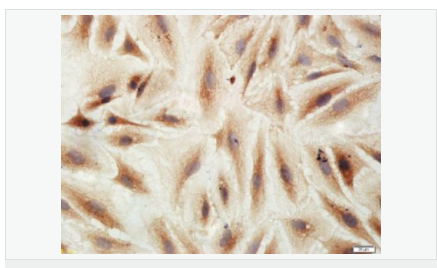

| 產(chǎn)品應(yīng)用 | WB=1:500-2000 IHC-P=1:100-500 IHC-F=1:100-500 Flow-Cyt=3ug/test ICC=1:100-500 IF=1:100-500 (石蠟切片需做抗原修復(fù)) not yet tested in other applications. optimal dilutions/concentrations should be determined by the end user. |

| 產(chǎn)品介紹 | This gene encodes an adenosine receptor that is a member of the G protein-coupled receptor superfamily. This integral membrane protein stimulates adenylate cyclase activity in the presence of adenosine. This protein also interacts with netrin-1, which is involved in axon elongation. The gene is located near the Smith-Magenis syndrome region on chromosome 17. [provided by RefSeq, Jul 2008]. Function: Receptor for adenosine. The activity of this receptor is mediated by G proteins which activate adenylyl cyclase. Subcellular Location: Cell membrane; Multi-pass membrane protein. Similarity: Belongs to the G-protein coupled receptor 1 family. SWISS: P29275 Gene ID: 136 Database links: Entrez Gene: 136 Human Omim: 600446 Human SwissProt: P29275 Human Unigene: 167046 Human Important Note: This product as supplied is intended for research use only, not for use in human, therapeutic or diagnostic applications. |